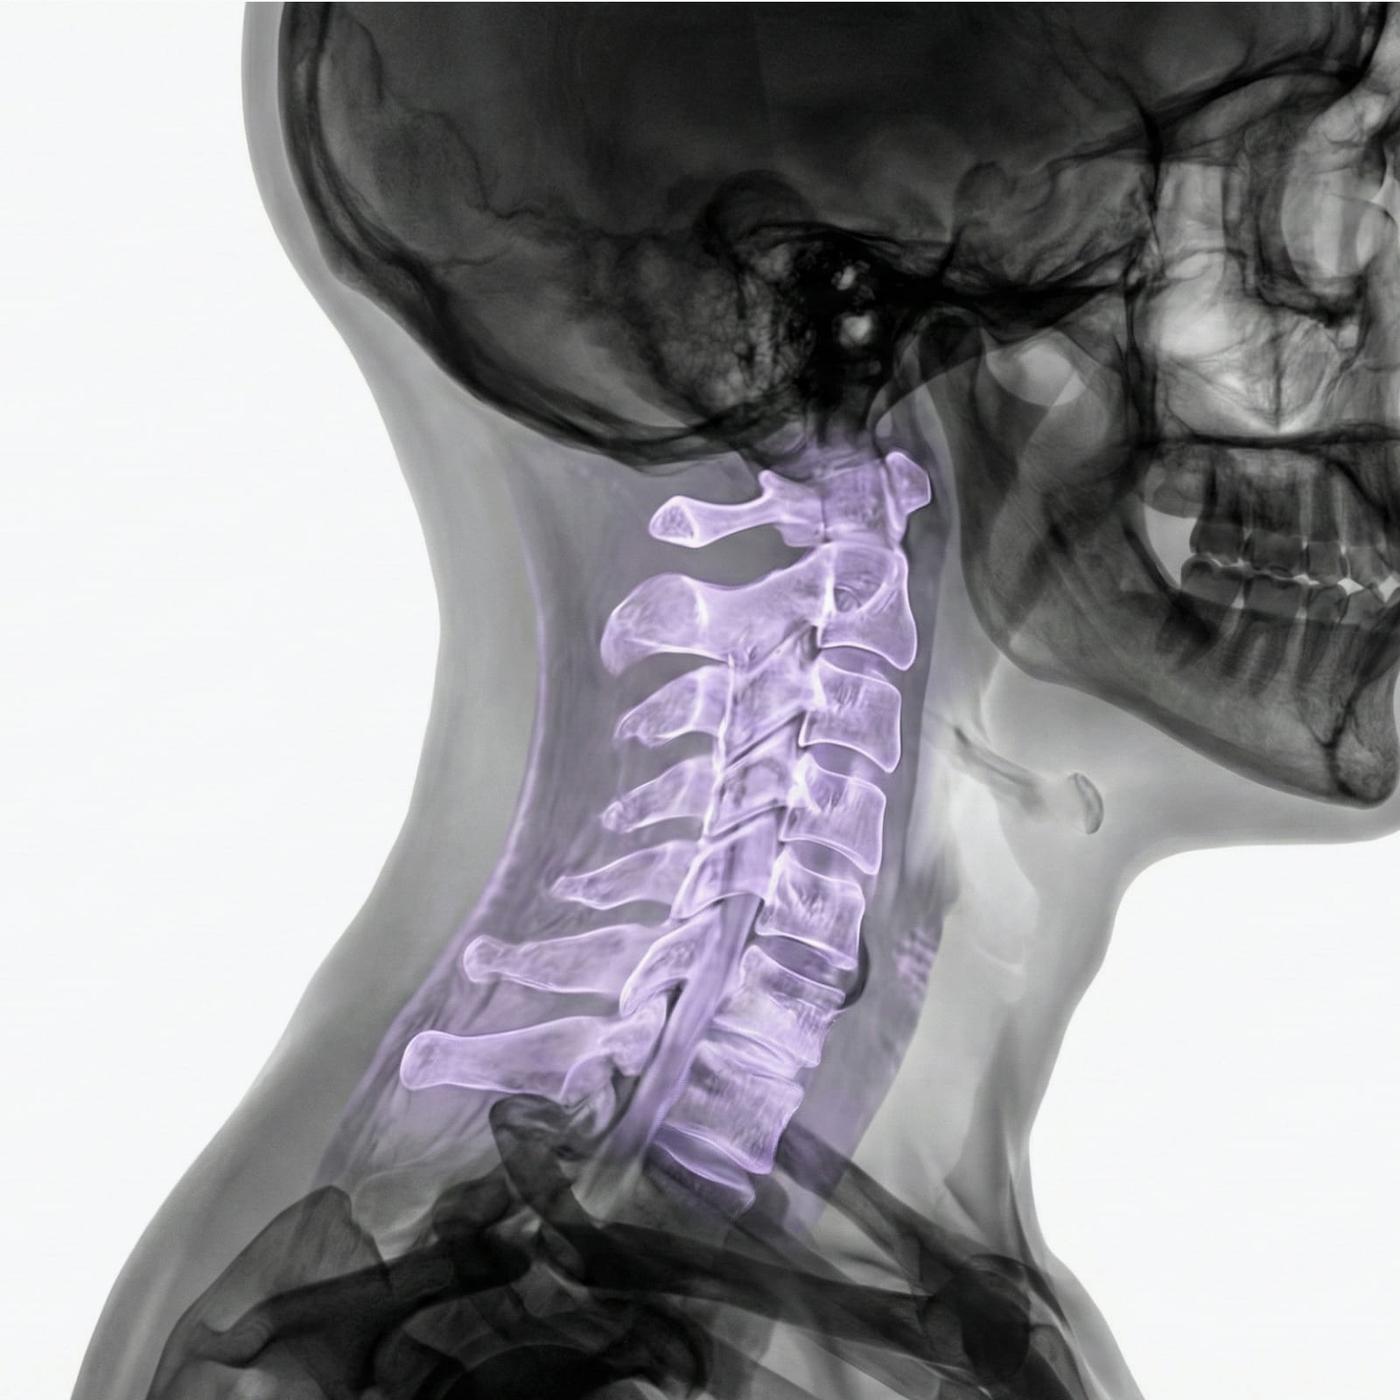

MRI Cervical Spine – Magnetic Resonance Imaging for Neck Pain, Stiffness or Nerve Symptoms in the Arms and Hands

The examination provides detailed images of the cervical vertebrae, discs, spinal cord, nerve roots and surrounding soft tissues. Since MRI does not use X-rays, it is also suitable for repeated examinations or for patients where radiation freedom is especially important.